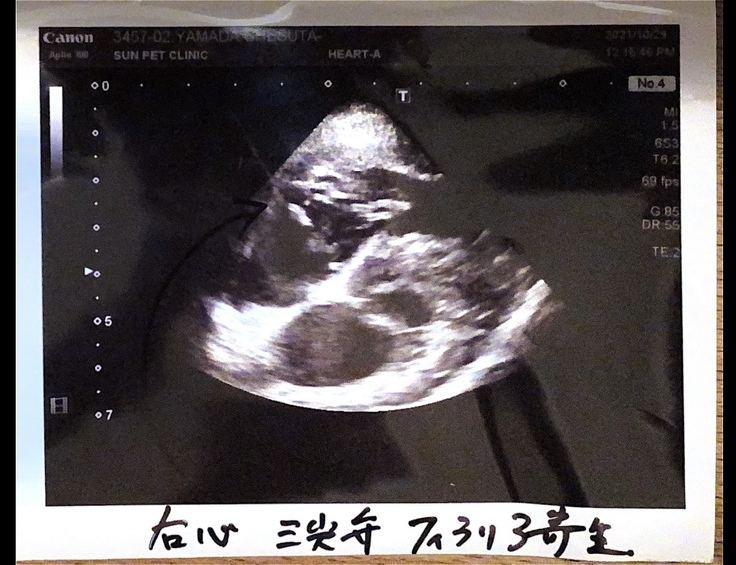

◯2021年10月29日

エコー写真を見て発覚したのは、フィラリア成虫が右心房から右心室に流れる間にある弁(三尖弁)に大量に絡みついており、弁がしっかり閉じられていないという状態になっていました。

↓黒いペンで書かれた矢印の先にある、白いグチャグチャに集まったものがフィラリア成虫です

そして、右心房から右心室に流れる度に閉じなければならない三尖弁が閉じない

↓

血液の80%は流れるけど20%は右心房に逆流する

でも右心房には次に流れてくる100%の血液が待ち構えている

逆流した20%と100%の血液を合わせて、毎回120%のポンプ運動で心臓が動いている

そのせいで、本来あるべき心臓のサイズから考えられないくらい変わってしまい、かなり圧迫している状態になってしまっているとのことでした。